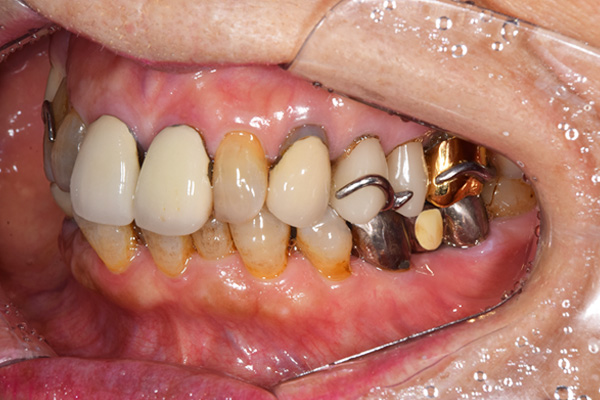

ケース3(インプラントを用いた部分入れ歯)

右上と左下の歯がない方です。 上の入れ歯の安定が悪く、作り直したいとのことでいらっしゃいました。 今お使いの上の入れ歯を見てみると、口蓋部分が抜けており、安定性に欠ける構造になっていました。この入れ歯はノンメタルクラスプデンチャーといって、金属のバネを使用しない 入れ歯になります。これは見た目は良いのですが、歯への負担が大きいことと、入れ歯自体がやわらかいため、噛むには不便なことがあります。

入れ歯は極力薄くするために金属を使用しました。しっかり噛める様にするため、ノンメタルクラスプデンチャーにはしませんでした。

上の入れ歯(表)

上の入れ歯(裏)

下の入れ歯

入れ歯を入れた状態のお口の中の写真です。バネも極力目立たないように作成しています。

年齢 70代・女性

主訴 上の入れ歯の安定が悪く、作り直したい

治療期間 5ヶ月

治療費 .診査診断:55,000円

.インプラント埋入:165,000円

.アバットメント:33,000円

.義歯:330,000円

治療方針 右片側のみ奥歯がない方です。

この様な場合入れ歯は反対側に維持を求めるため、大きな入れ歯になりがちです。

そのため違和感が強いことがおおいです。

また、片側だけないですので、安定もむずかしくなります。

そこで、安定をよくするために、右の奥歯の位置にインプラントをいれて、義歯が揺れない様にすることにしました。

治療内容 レントゲンをみて最低限の長さのインプラントを右上の奥歯の位置に埋入しました。インプラントと骨の結合(オッセオインテグレーション)と歯肉の治癒を待ち、アバットメントをいれて型取りをして、入れ歯を作成しました。極力薄くするために、金属をもちいた入れ歯にしました。

特記事項 インプラントは必ず成功するというものではありません。 また治癒も人それぞれで、長くかかることもあります。 入れ歯を入れ終わったあとも、アバットメントが緩んできたり、入れ歯が歯ぐきにあたって痛いところもでてきますので、調整は必要になります。